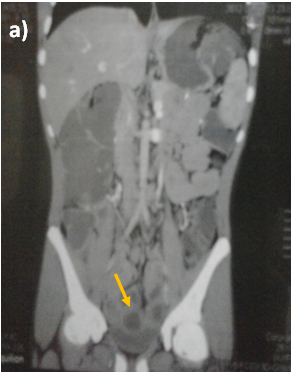

Abdominal ultrasound showed uniform circumferential mural thickening of the small bowel loops, so we proceeded to C.T Enterography. As shown in Figure 1, there is diffuse uniform thickening of the small bowel loops mainly involving the ileum with no focal thickening or masses. Then upper endoscopy and colonoscopy were performed to the patient and they showed multiple tiny rounded nodules at the terminal ileum that were biopsied and revealed non-specific inflammation free of granuloma or malignancy. Then we proceeded to double balloon enteroscopy which was done by an over tube double balloon Fuji series endoscopy, which proceeded to about 200cm from the duodenal bulb. Double balloon endoscopy as shown in Figure 2, showed numerous visible mucosal nodules measuring few millimeters in diameter involving the whole part of the small intestine examined which were biopsied. Histopathology revealed chronic inflammatory enteritis with foci of lymphoid aggregates with no atypia or malignancy (Table 1).

Figure 1 C.T. Enterography of the patient that showed diffuse uniform thickening of the small bowel loops mainly involving the ileum with no focal thickening or masses.